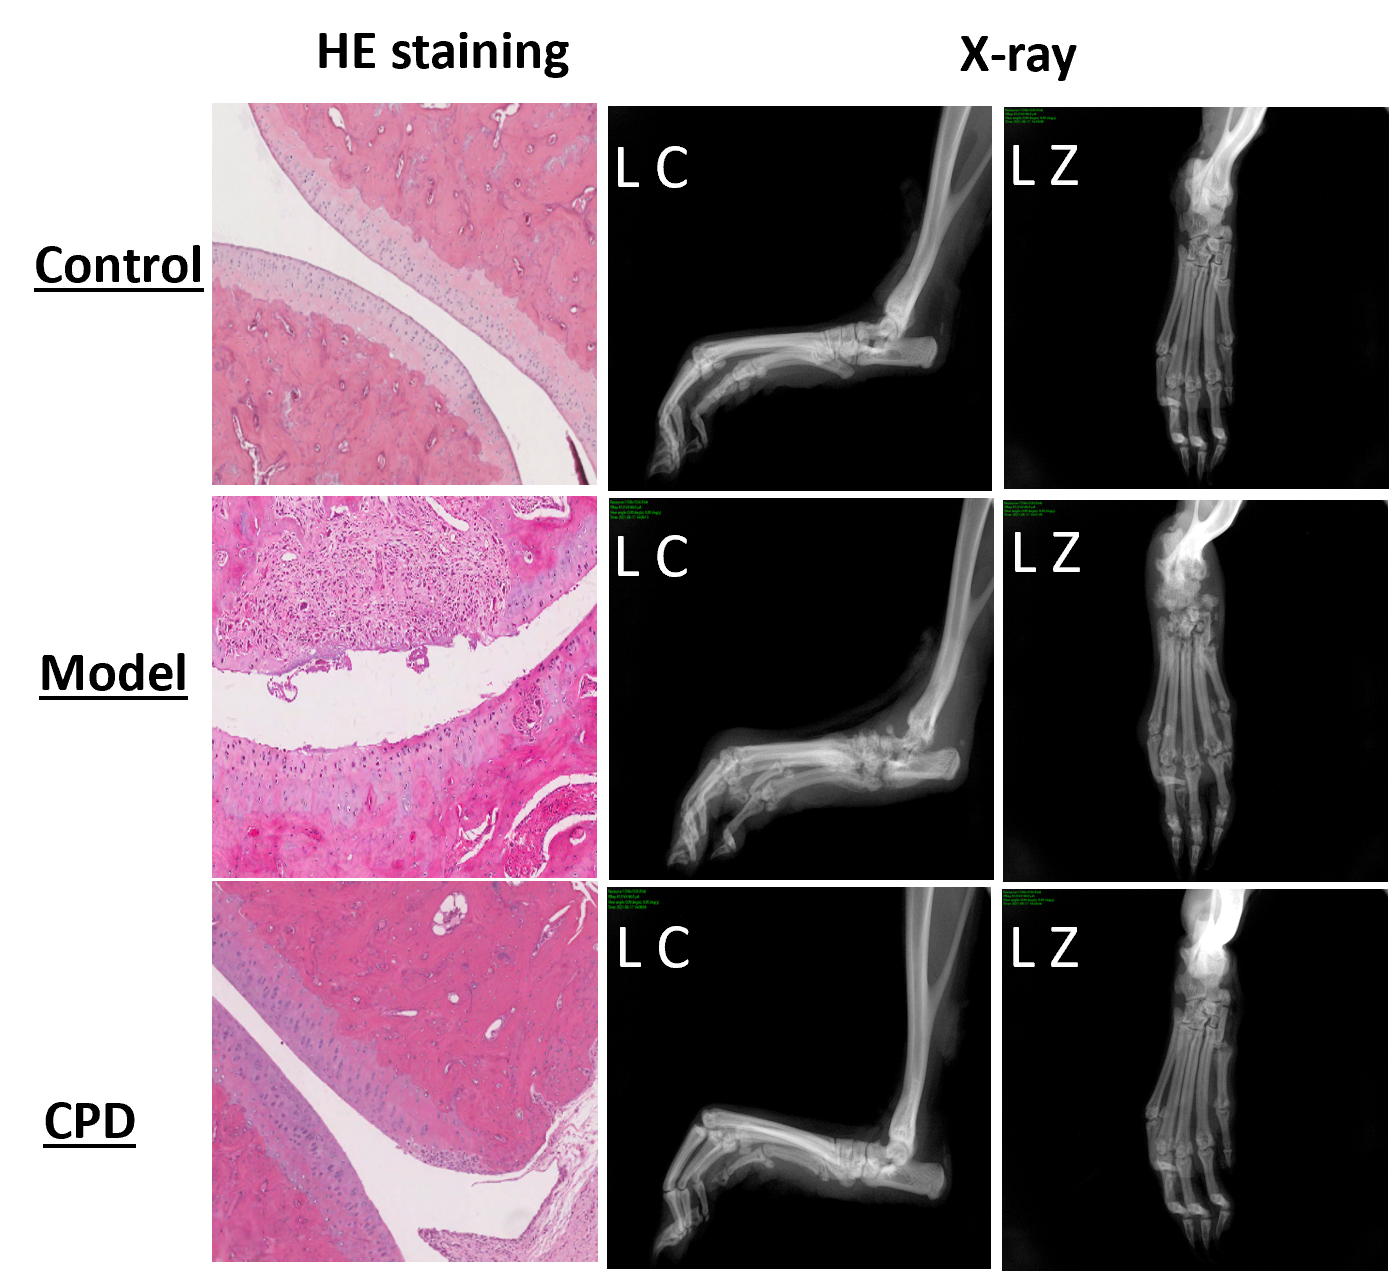

The model changes are also observable directly during the anatomical and histopathological evaluation below (CPD = tofacitinib).

Model anatomy and histopathological analysis confirm model adequacy for preclinical RA compound testing.

Also, both clinical score and joint swelling show model relevancy for RA and responsiveness to tofacitinib, a Janus kinase (JAK) inhibitor.